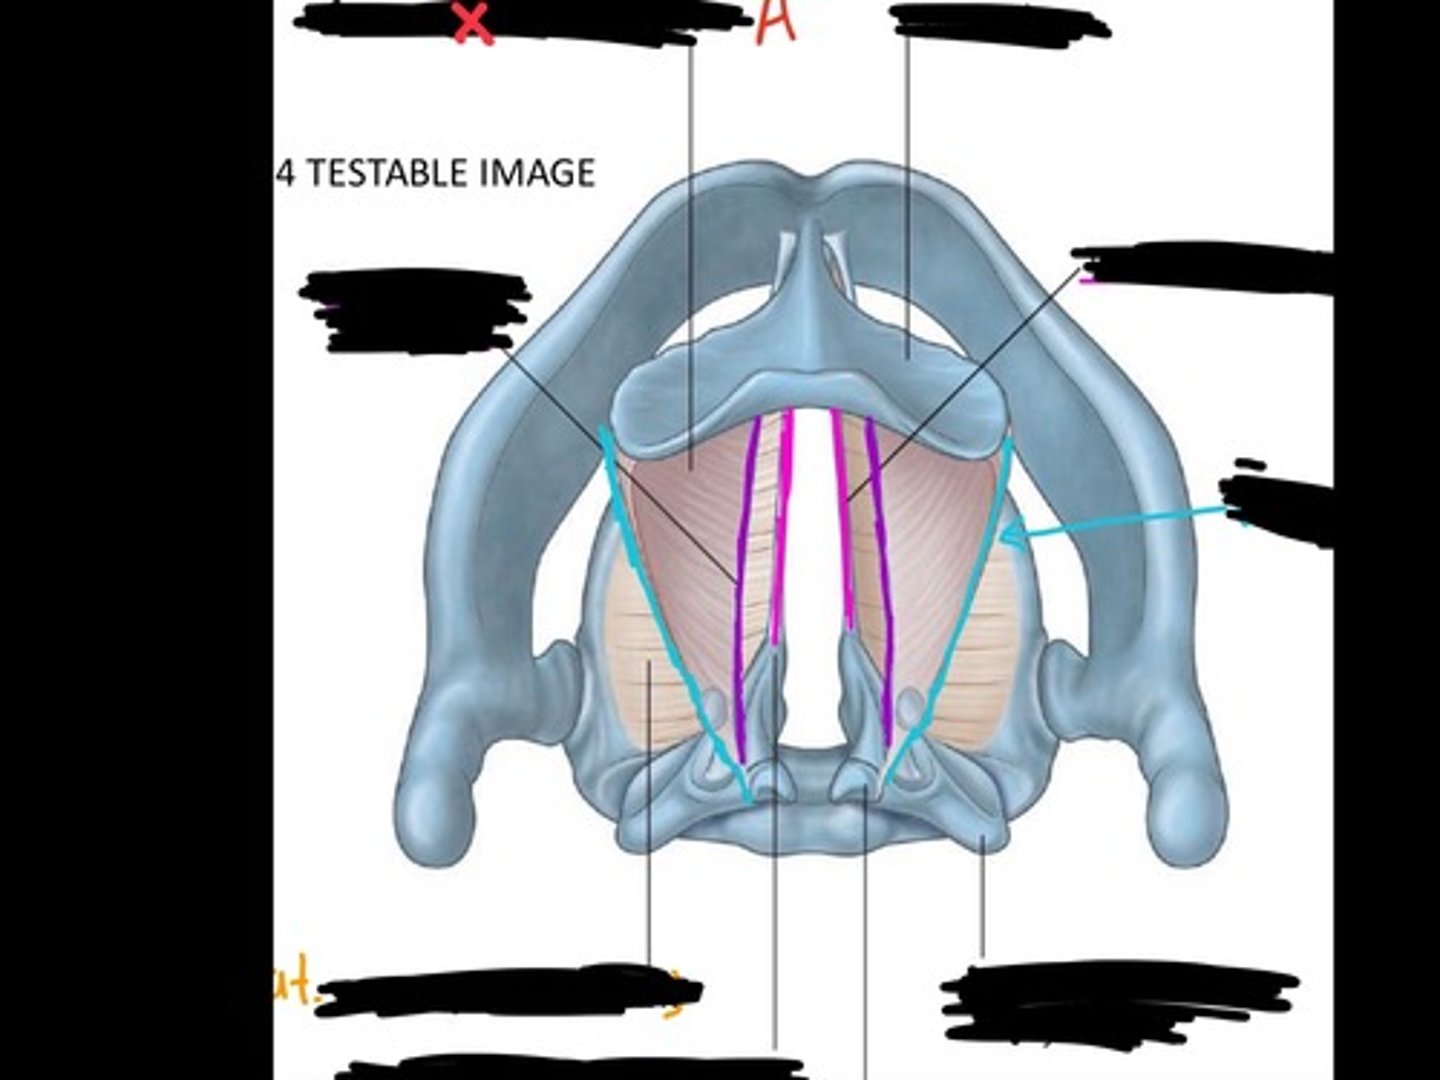

Vocal process of arytenoid

Conus elasticus

Vestibular ligament

Quadrangular membrane

Epiglottis

vocal ligament

Aryepiglottic ligament

Muscular process of arytenoid

Corniculate cartilage

Posterior crico arytenoid

oblique arytenoid

transverse artyenoid

Rima glottidis

Vocal ligament

Vocalis muscle

Lateral cricothyroid ligament

Lateral cricoartenoid